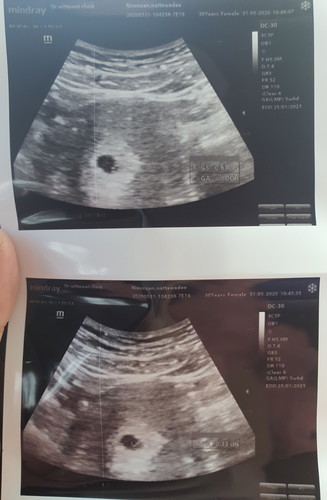

6week

พึ่งไปซาวด์มาค่ะ คุณหมอบอกนับตามรอบ ปจด 6week พอดี เห็นแต่ถุงตั้งครรภ์ กับถุงไข่แดง ยังคงต้องลุ้นกันต่อไปใช่ไหมคะ ?

ใช่ค่ะ 6Wยังเล็กมากๆ ครั้งหน้าน่าจะเห็นหัวใจค่ะ